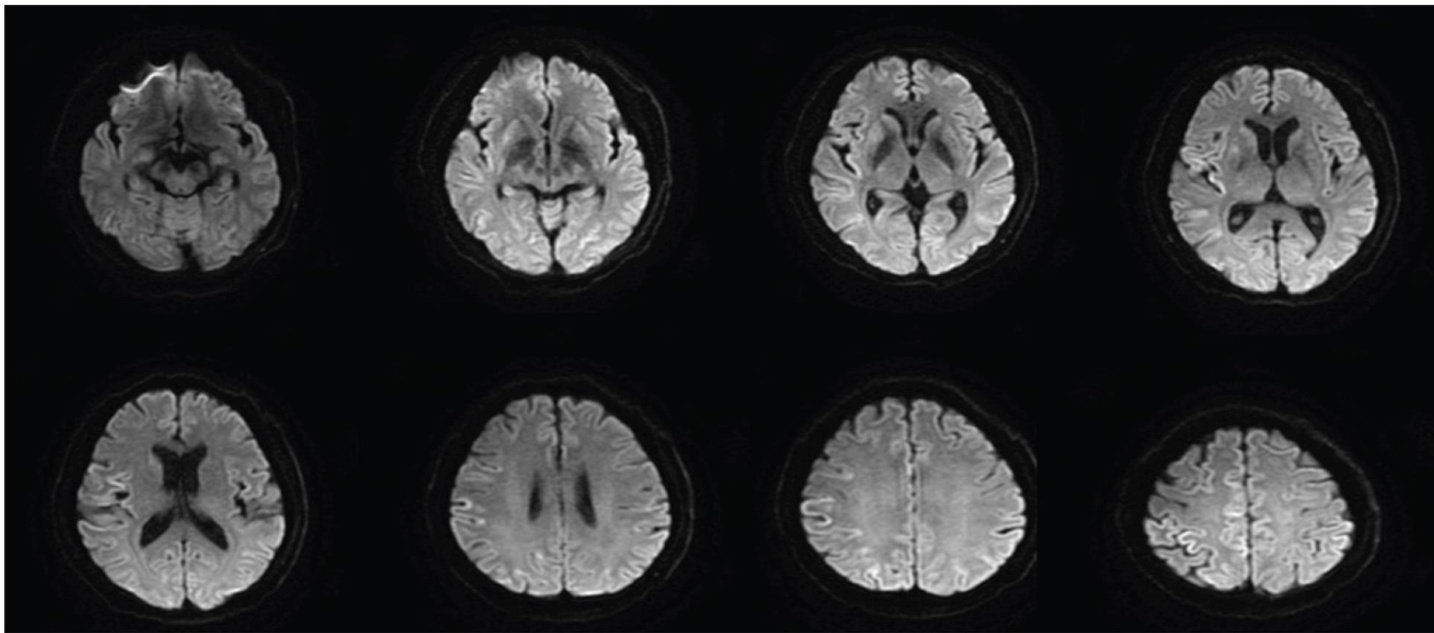

摘要克-雅脑病(CJD)首发症状不典型,给早期诊断及鉴别带来了较大难度。步态1例以头晕、行走不稳的小脑性共济失调症状起病的散发型CJD。